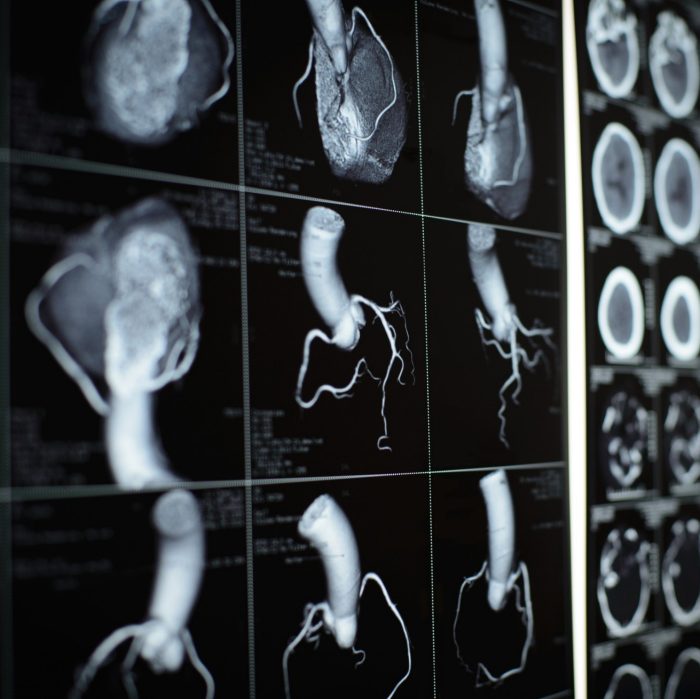

CT images on black film of human heart and coronary artery